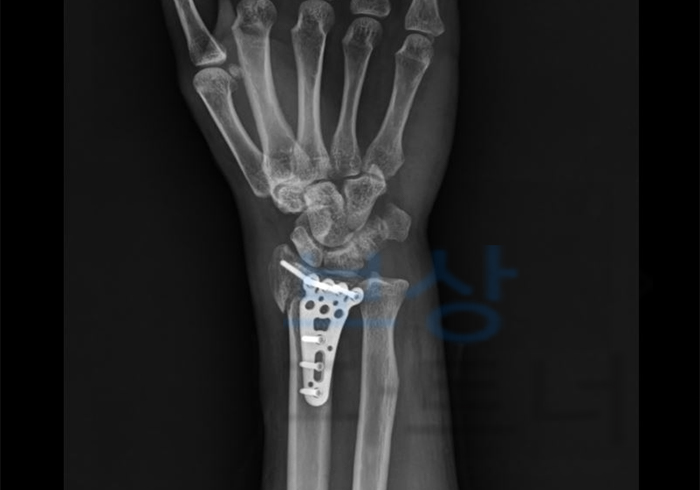

K 님은 건설 현장에서 일하시던 중, 발코니에서 넘어져서 손목을 다치게 되셨습니다.

병 명:

요골 하단의 상세불명의 골절, 폐쇄성

손목 및 수근골 인대의 외상성 파열

기타 손가락의 근위지골 골절, 폐쇄성

K 님은 이 사고로 손목에 금속판으로 내고정술을 받게 되셨습니다. 작업 중 사고이기 때문에 당연히 산재 승인을 받아서 처리할 수 있었습니다. 이 사고로 받으신 산재보험 항목은 요양급여(치료비), 휴업급여, 장해급여입니다. 금액을 모두 합치면 3,300만 원 정도 되었습니다.